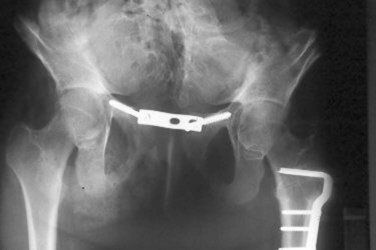

Infants who are medically stable may be considered for urinary tract reconstruction in the immediate postnatal period. Osteotomy is indicated in all children with cloacal exstrophy at the time of bladder closure because of the wide diastasis that is invariably present (Mathews et al, 1998). Osteotomy allows the pelvic ring, bladder, and abdominal wall to be closed without undue tension on the closure. Reduction in dehiscence and postoperative ventral hernias has been noted in patients treated with osteotomy. In a large series reported by Ben-Chaim and colleagues (1995c), significant complications occurred in 89% of patients who underwent closure of the cloacal exstrophy without osteotomy but in only 17% of patients who underwent osteotomy at the time of initial cloacal exstrophy closure. Interestingly, the patients who underwent osteotomy and those who did not were similar in terms of size of the omphalocele, presence of myelomeningocele, and time of primary closure. However, it is not surprising that osteotomy had no effect on eventual continence of patients with cloacal exstrophy.

Currently, combined anterior innominate and vertical iliac osteotomies are routinely used at our institution (Silver et al, 1999). This approach does not require the patient to be repositioned on the operating table before commencing bladder and abdominal wall closure. In addition, this method obviates the use of a posterior approach and any complication of the procedure related to the spinal or back closure. In a series of five patients with extreme pubic diastasis greater than 10 cm, Silver and colleagues (1999) described initial pelvic osteotomy and gradual pelvic closure of the fixator for 1 to 2 weeks, followed by abdominal wall closure and bladder closure. Closure was successful in all patients without technical problems or complications. This technique of staged pelvic closure may provide reliable initial secondary repair in patients with cloacal exstrophy in whom one-stage pelvic closure is not feasible, even with pelvic osteotomy. An interpubic stainless bar has been added to permit stabilization of the pubic approximation and maintain the reduction in diastasis (Fig. 124–31) (Mathews et al, 2005). Because of the possible asymmetry that can be noted in the pelvic bones, care must be used when performing osteotomies and fixation. In patients who have lower extremity abnormalities, providing postoperative traction can also be challenging.